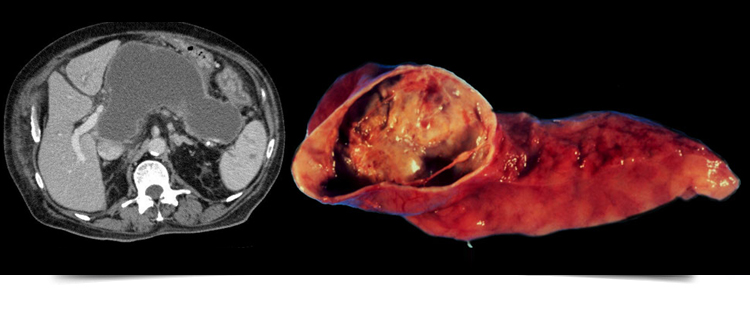

PANCREATIC PSEUDOCYST

A pancreatic pseudocyst is a circumscribed collection of fluid rich in pancreaticenzymes, blood, and necrotic tissue, typically located in the lesser sac of the abdomen. Pancreatic pseudocysts are usually complications of pancreatitis, although in children they frequently occur following abdominal trauma.

A pancreatic pseudocyst is a collection of tissue and fluids that forms on your pancreas. Your pancreas is located behind your stomach.

Pseudocysts usually form as the result of a hard blow to your abdomen or an inflammation of the pancreas known as pancreatitis.

Pseudo” means false. A pseudocyst looks like a cyst but is made from different kinds of tissue than a true cyst. A true cyst is more likely to be cancerous than a pseudocyst.